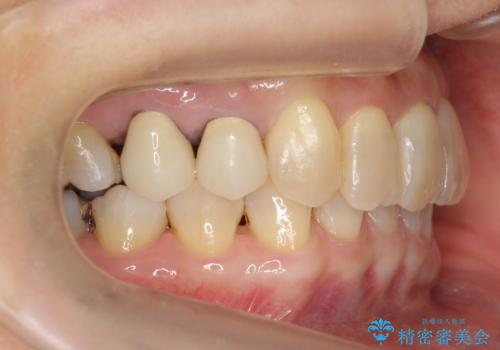

50代女性 インビザライン かみ合わせが深く、難しい症例

かみ合わせが深く、上の歯が咬みこんで下の歯にワイヤーがつけられない状態で、ワイヤー矯正はかなり難しい状態でした。

反対咬合や、すれ違い咬合もあり、大変難しいケースでしたが治療することができました。

かみ合わせが深い方はもともとかみしめが強く、マウスピース矯正を長期にすると、奥歯が咬まなくなってくる症状が強くなります。

今回もそういった状態になったのを、装着時間や歯の移動を工夫する形で治療しました。